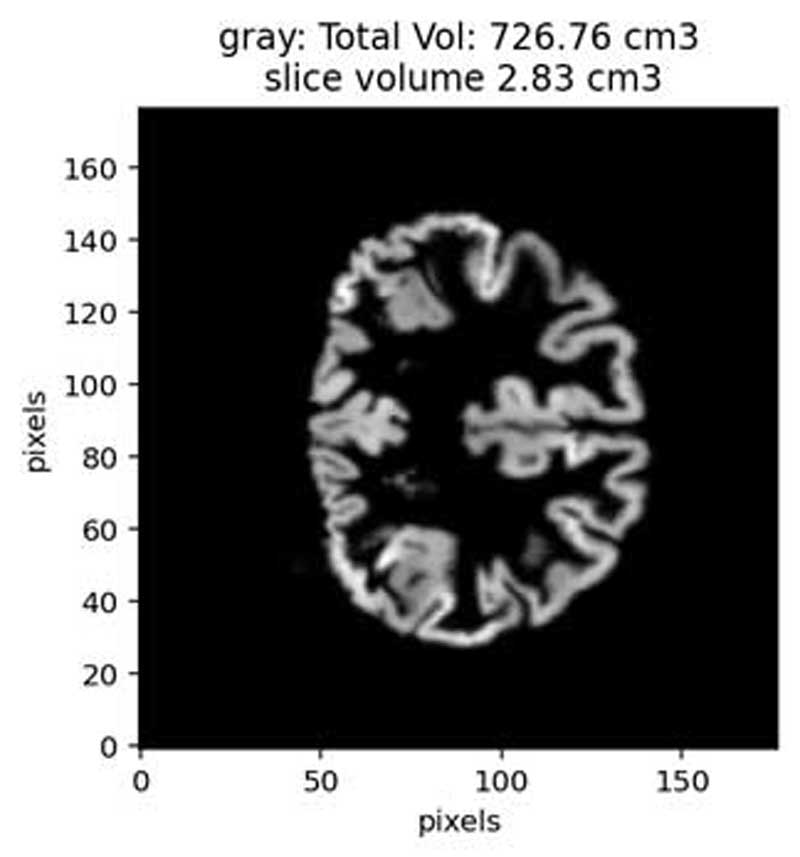

My research integrates advanced neurophysiological and microscopic techniques, with histology and cutting-edge signal processing analysis to explore the fundamental aspects of brain function under health and disease. I focus on cellular communication and network dynamics and interrogate the interplay between intrinsic ionic mechanisms, synaptic transmission and native glial dynamics in relation to physiological and pathophysiological states in neurodegenerative disorders such as multiple sclerosis, Parkinson’s and Alzheimer’s Disease.